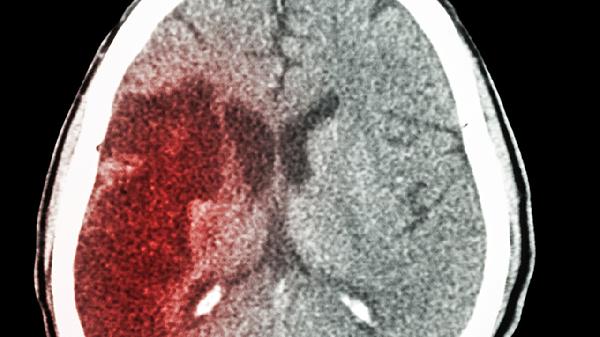

宝宝严重脑积水通常表现为头围异常增大、前囟门膨隆、落日征、呕吐和发育迟缓等症状。脑积水是指脑脊液在脑室系统内积聚过多,导致颅内压增高,可能由先天性畸形、感染、出血或肿瘤等因素引起。

家长发现宝宝出现上述症状应及时就医,通过头颅超声、CT或MRI检查明确诊断。治疗需根据病因选择脑室腹腔分流术或第三脑室造瘘术等手术方式,术后需定期随访评估分流管功能及神经发育状况。日常护理中注意避免头部碰撞,监测头围变化,保证营养支持,并按医嘱进行运动功能训练和认知刺激。